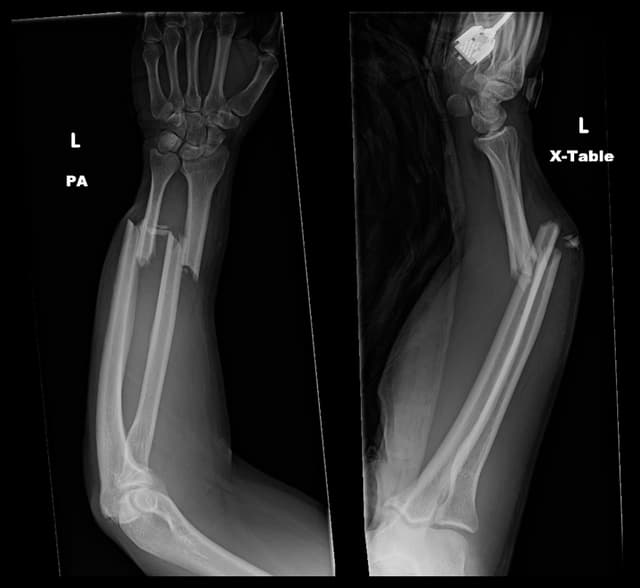

Imaging

Pre-op